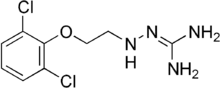

Guanoclor (INN), also known as guanochlor, is a sympatholytic drug. It is known to bind to non-adrenergic sites in pig kidney membranes.[1]

When β-(2,6-dichlorophenoxy)ethyl bromide (1) is reacted with hydrazine to give 2, and this is reacted with S-methylthiourea, guanochlor (3) results.[2][3]